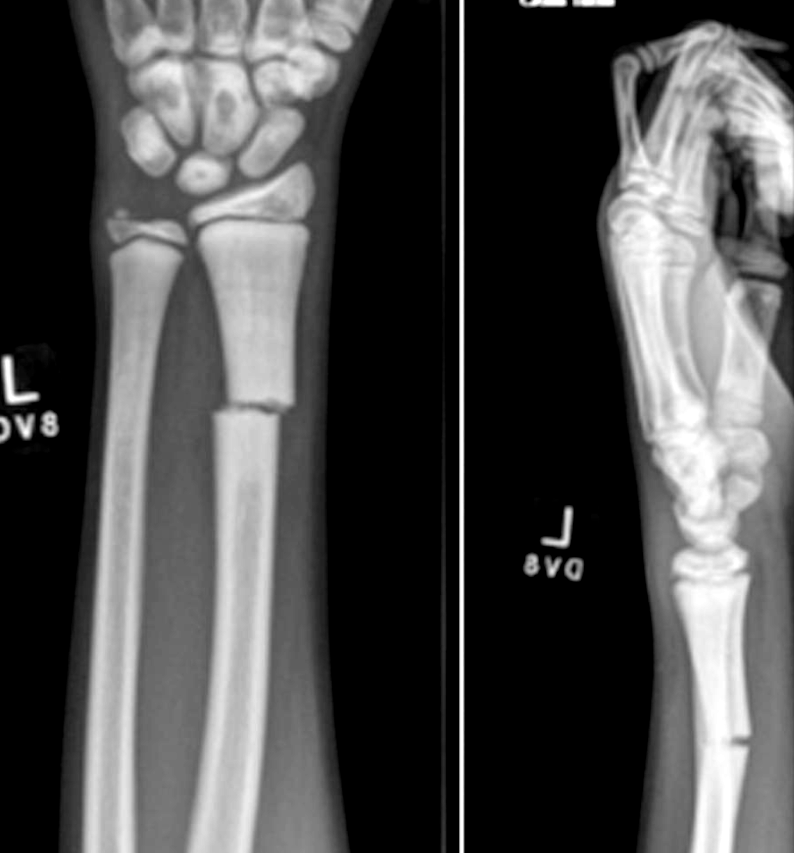

Fractura de escafoides pediátrica asociada con osteopetrosis: reporte de un caso

Un niño de 12 años con osteopetrosis sufrió una fractura de cintura de escafoides, que no se había informado previamente con esta afección. La cicatrización se logró con éxito con la fijación percutánea con tornillos de compresión canulados, aunque con una cicatrización prolongada como es típico de esta afección.

La falta de remodelación osteoclástica predispone a los pacientes con osteopetrosis a sufrir fracturas, comúnmente en huesos largos. El aumento de los riesgos de infección, anestesia y material roto junto con la capacidad limitada para comprimir el hueso pueden desalentar el tratamiento quirúrgico. La fijación interna aún debe considerarse en casos seleccionados para limitar el desplazamiento al tiempo que permite un rango de movimiento temprano.